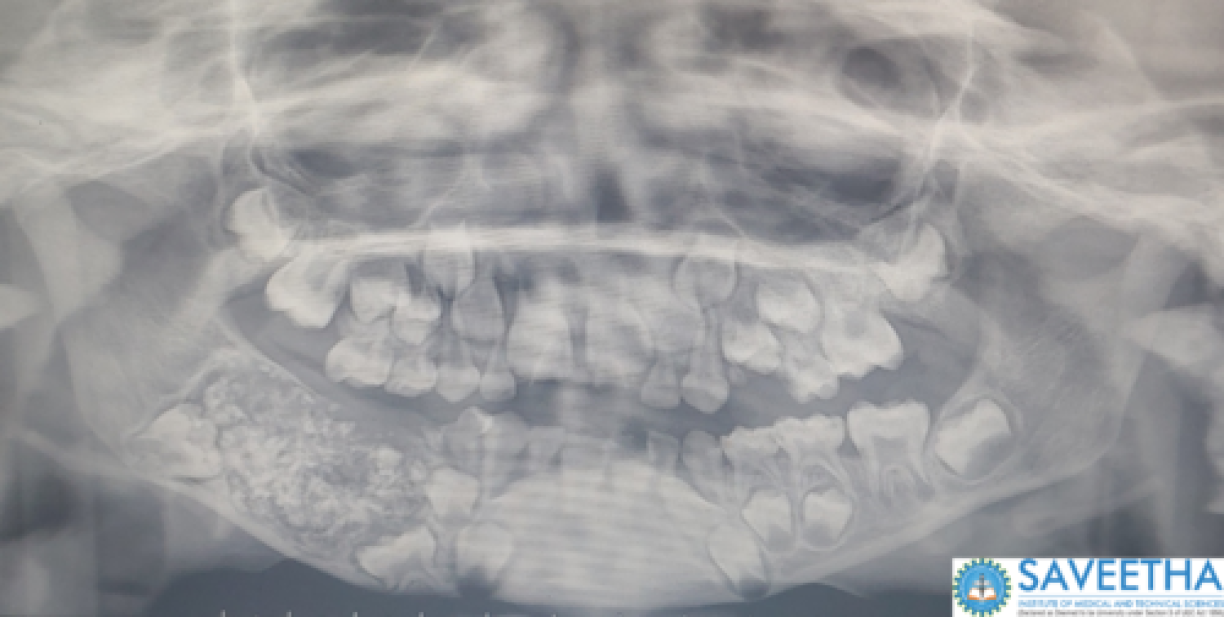

Les médecins ont pu identifier la masse, d’environ 200 grammes, et lui ont retiré après cinq heures d’opération permettant de préserver sa mâchoire. L’excroissance contenait 526 dents, toutes formées d’une structure avec une racine, de l’émail et une couronne. La plus petite mesurait environ 0,1 millimètre quand la plus grande mesurait 1,5 centimètre.